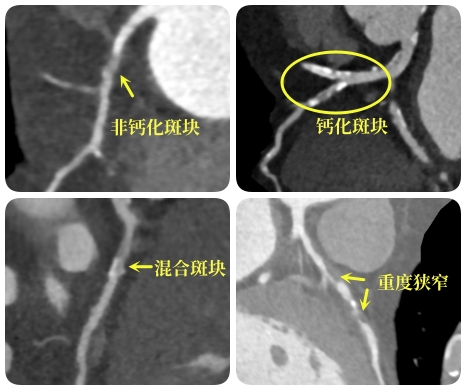

冠脉行走于心脏表面,分成左右两支,源源不断地为心脏输送新鲜血液。当冠脉处发生病变,如硬化、钙化、形成斑块时,会导致冠脉管腔狭窄甚至闭塞,血液无法正常提供给心脏,从而导致心肌缺血、缺氧甚至坏死等一系列重大问题!

冠脉CTA可以很好地观察冠状动脉是否有硬化、钙化、斑块情况以及管腔是否狭窄、闭塞,也可以评估冠状动脉支架或搭桥术后血管情况,在临床上准确率可以高达90%以上。